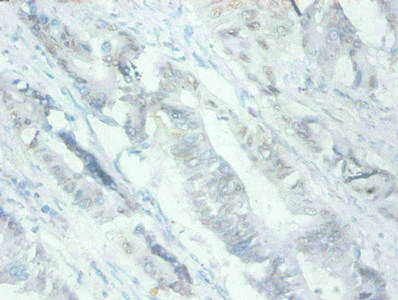

圖片:

產品描述:MFGE8單克隆抗體(CUSABIO貨號:CSB-MA079741A0m)是針對乳脂肪球EGF因子8蛋白研發的科研專用試劑,該靶標蛋白在細胞粘附、信號傳導及免疫調節中發揮重要作用,尤其參與脂質代謝相關通路和細胞間相互作用機制研究。本產品采用高特異性單克隆抗體技術,經嚴格驗證可識別人源MFGE8抗原表位,適用于酶聯免疫吸附測定(ELISA)進行蛋白質定量分析,以及免疫組化(IHC)實驗用于組織定位研究。其核心優勢包括精準的抗原結合能力與穩定的批次一致性,能夠滿足細胞生物學、腫瘤微環境、代謝疾病等領域的科研需求,特別適用于乳腺組織、免疫細胞及相關病理模型的分子機制探索。該抗體為凍干粉劑型,建議用戶根據實驗體系優化使用方案,通過靶向MFGE8蛋白的功能解析,助力細胞信號網絡、組織修復機制等前沿課題研究。

應用范圍:ELISA,IHC

Application Recommended Dilution IHC 1:50-1:500 -